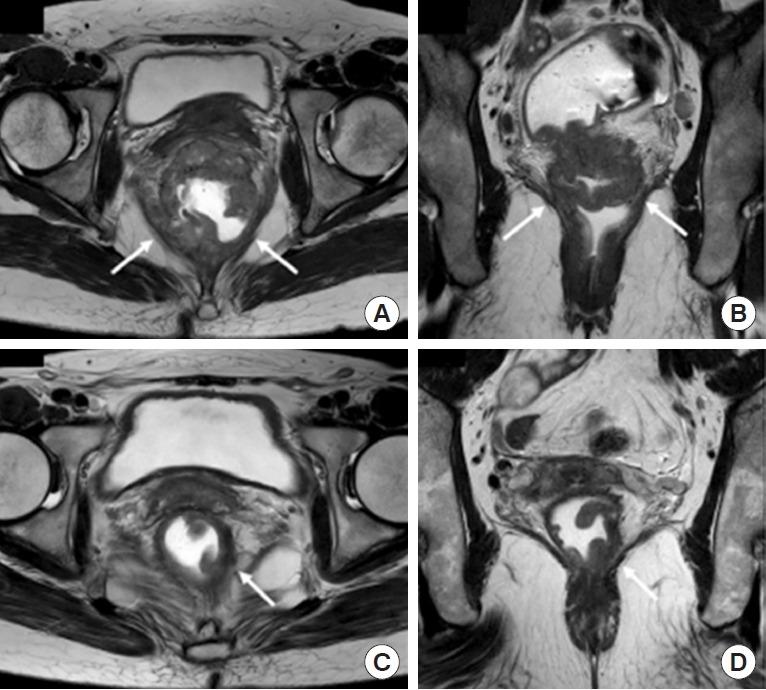

Despite innovative advancements, distally located rectal cancer remains a critical disease of challenging management. The crucial location of the tumor predisposes it to a circumferential resection margin (CRM) that tends to involve the anal sphincter complex and surrounding organs, with a high incidence of delayed anastomotic complications and the risk of the pelvic sidewall or rarely inguinal lymph node metastases. In this regard, colorectal surgeons should be aware of other issues beyond total mesorectal excision (TME) performance. For decades, the concept of extralevator abdominoperineal resection to avoid compromised CRM has been introduced. However, the complexity of deep pelvic dissection with poor visualization in low-lying rectal cancer has led to transanal TME. In contrast, neoadjuvant chemoradiotherapy (NCRT) has allowed for the execution of more sphincter-saving procedures without oncologic compromise. Significant tumor regression after NCRT and complete pathologic response also permit applying the watch-and-wait protocol in some cases, now with more solid evidence. This review article will introduce the current surgical treatment options, their indication and technical details, and recent oncologic and functional outcomes. Lastly, the novel characteristics of distal rectal cancer, such as pelvic sidewall and inguinal lymph node metastases, will be discussed along with its tailored and individualized treatment approach.

尽管有创新性进展,但低位直肠癌仍然是一种管理具有挑战性的关键疾病。肿瘤的关键位置使其易出现环周切缘(CRM)累及肛门括约肌复合体和周围器官的情况,吻合口延迟并发症的发生率很高,且存在盆腔侧壁或极少出现的腹股沟淋巴结转移风险。在这方面,结直肠外科医生应意识到全直肠系膜切除(TME)操作之外的其他问题。几十年来,为避免CRM受损而引入了经肛提肌腹会阴联合切除术的概念。然而,低位直肠癌深部盆腔解剖的复杂性以及视野不佳导致了经肛全直肠系膜切除术的出现。相比之下,新辅助放化疗(NCRT)使得在不影响肿瘤学疗效的情况下能够实施更多保留括约肌的手术。NCRT后显著的肿瘤退缩和完全病理缓解在某些情况下也允许采用观察等待方案,现在有了更确凿的证据。这篇综述文章将介绍当前的手术治疗选择、其适应证和技术细节,以及近期的肿瘤学和功能结局。最后,将讨论低位直肠癌的新特征,如盆腔侧壁和腹股沟淋巴结转移,以及其针对性的个体化治疗方法。